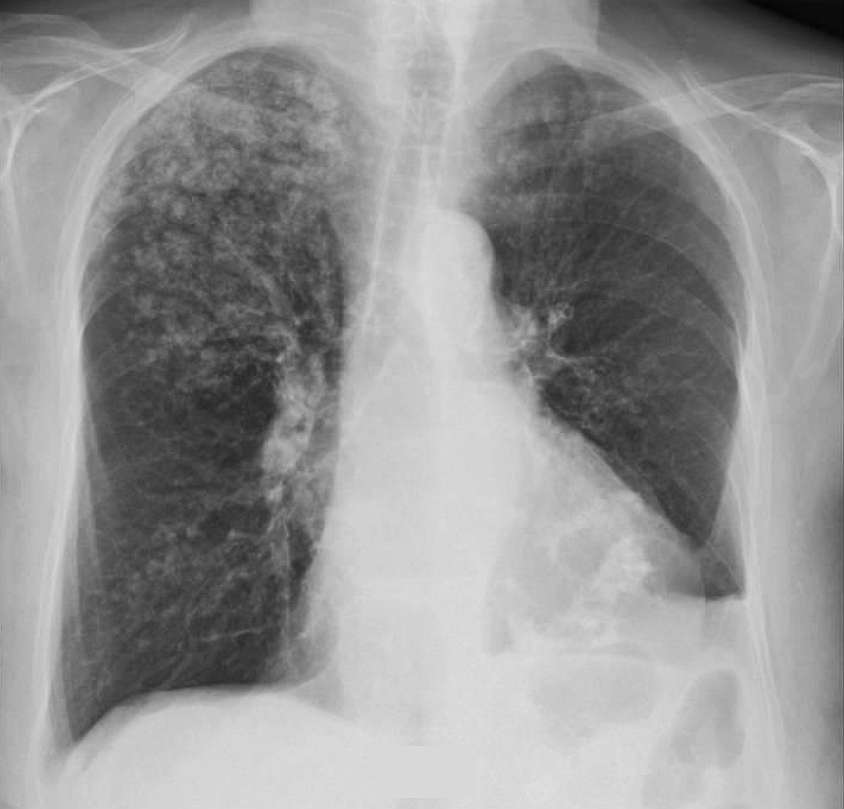

71-year-old Woman With Chronic Renal Failure Post category:Spot Diagnosis Post published:January 27, 2024 Share on Facebook Share on X (Twitter) Share on Pinterest Share on Email Share on Reddit Chest X-ray of a Woman With Chronic Renal Failure A 71-year-old woman presented with a non-healing wound at the hospital. She had a history of chronic pyelonephritis and chronic renal failure. She was treated with chronic haemodialysis-haemofiltration. What could be the diagnosis ? FULL CASE AND ANSWER Share on Facebook Share on X (Twitter) Share on Pinterest Share on Email Share on Reddit Read more articles Previous PostFever, Vomiting, Diarrhea and Subconjunctival Bleeding Next PostNonpruritic Hyperpigmented Plaques You Might Also Like Erythematous and Irregular Linear Streak Extending from the Hand to the Axilla December 21, 2021 Patient with Repeated Episodes of Septic Shock and History of Pulmonary Tuberculosis in the Past December 17, 2021 Patient with Symptoms of Eye and Ear Pain March 31, 2022